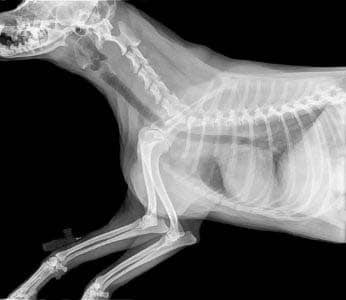

På klinikken foretages bedøvelser i forbindelse med tandrensninger og udtrækning af syge tænder, operationer og røntgenundersøgelser.